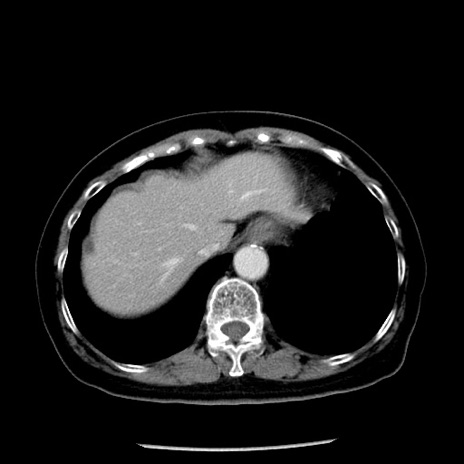

症例13(横断像)

【症例】70歳代女性

【主訴】腹痛、嘔吐

【現病歴】15時間程前(昨晩)より腹痛あり。今朝になっても症状の改善なく、嘔吐あり。腹痛も増悪あり、救急外来受診。

【既往歴】子宮癌全摘術後

【身体所見】意識清明、BP 121/72mmHg、P 74bpm、SpO2 100%(RA)、腹部:平坦・軟、腸雑音ほぼ聴取せず。下腹部・心窩部・臍左上に圧痛あり。反跳痛なし。

【データ】WBC 10600、CRP 0.15